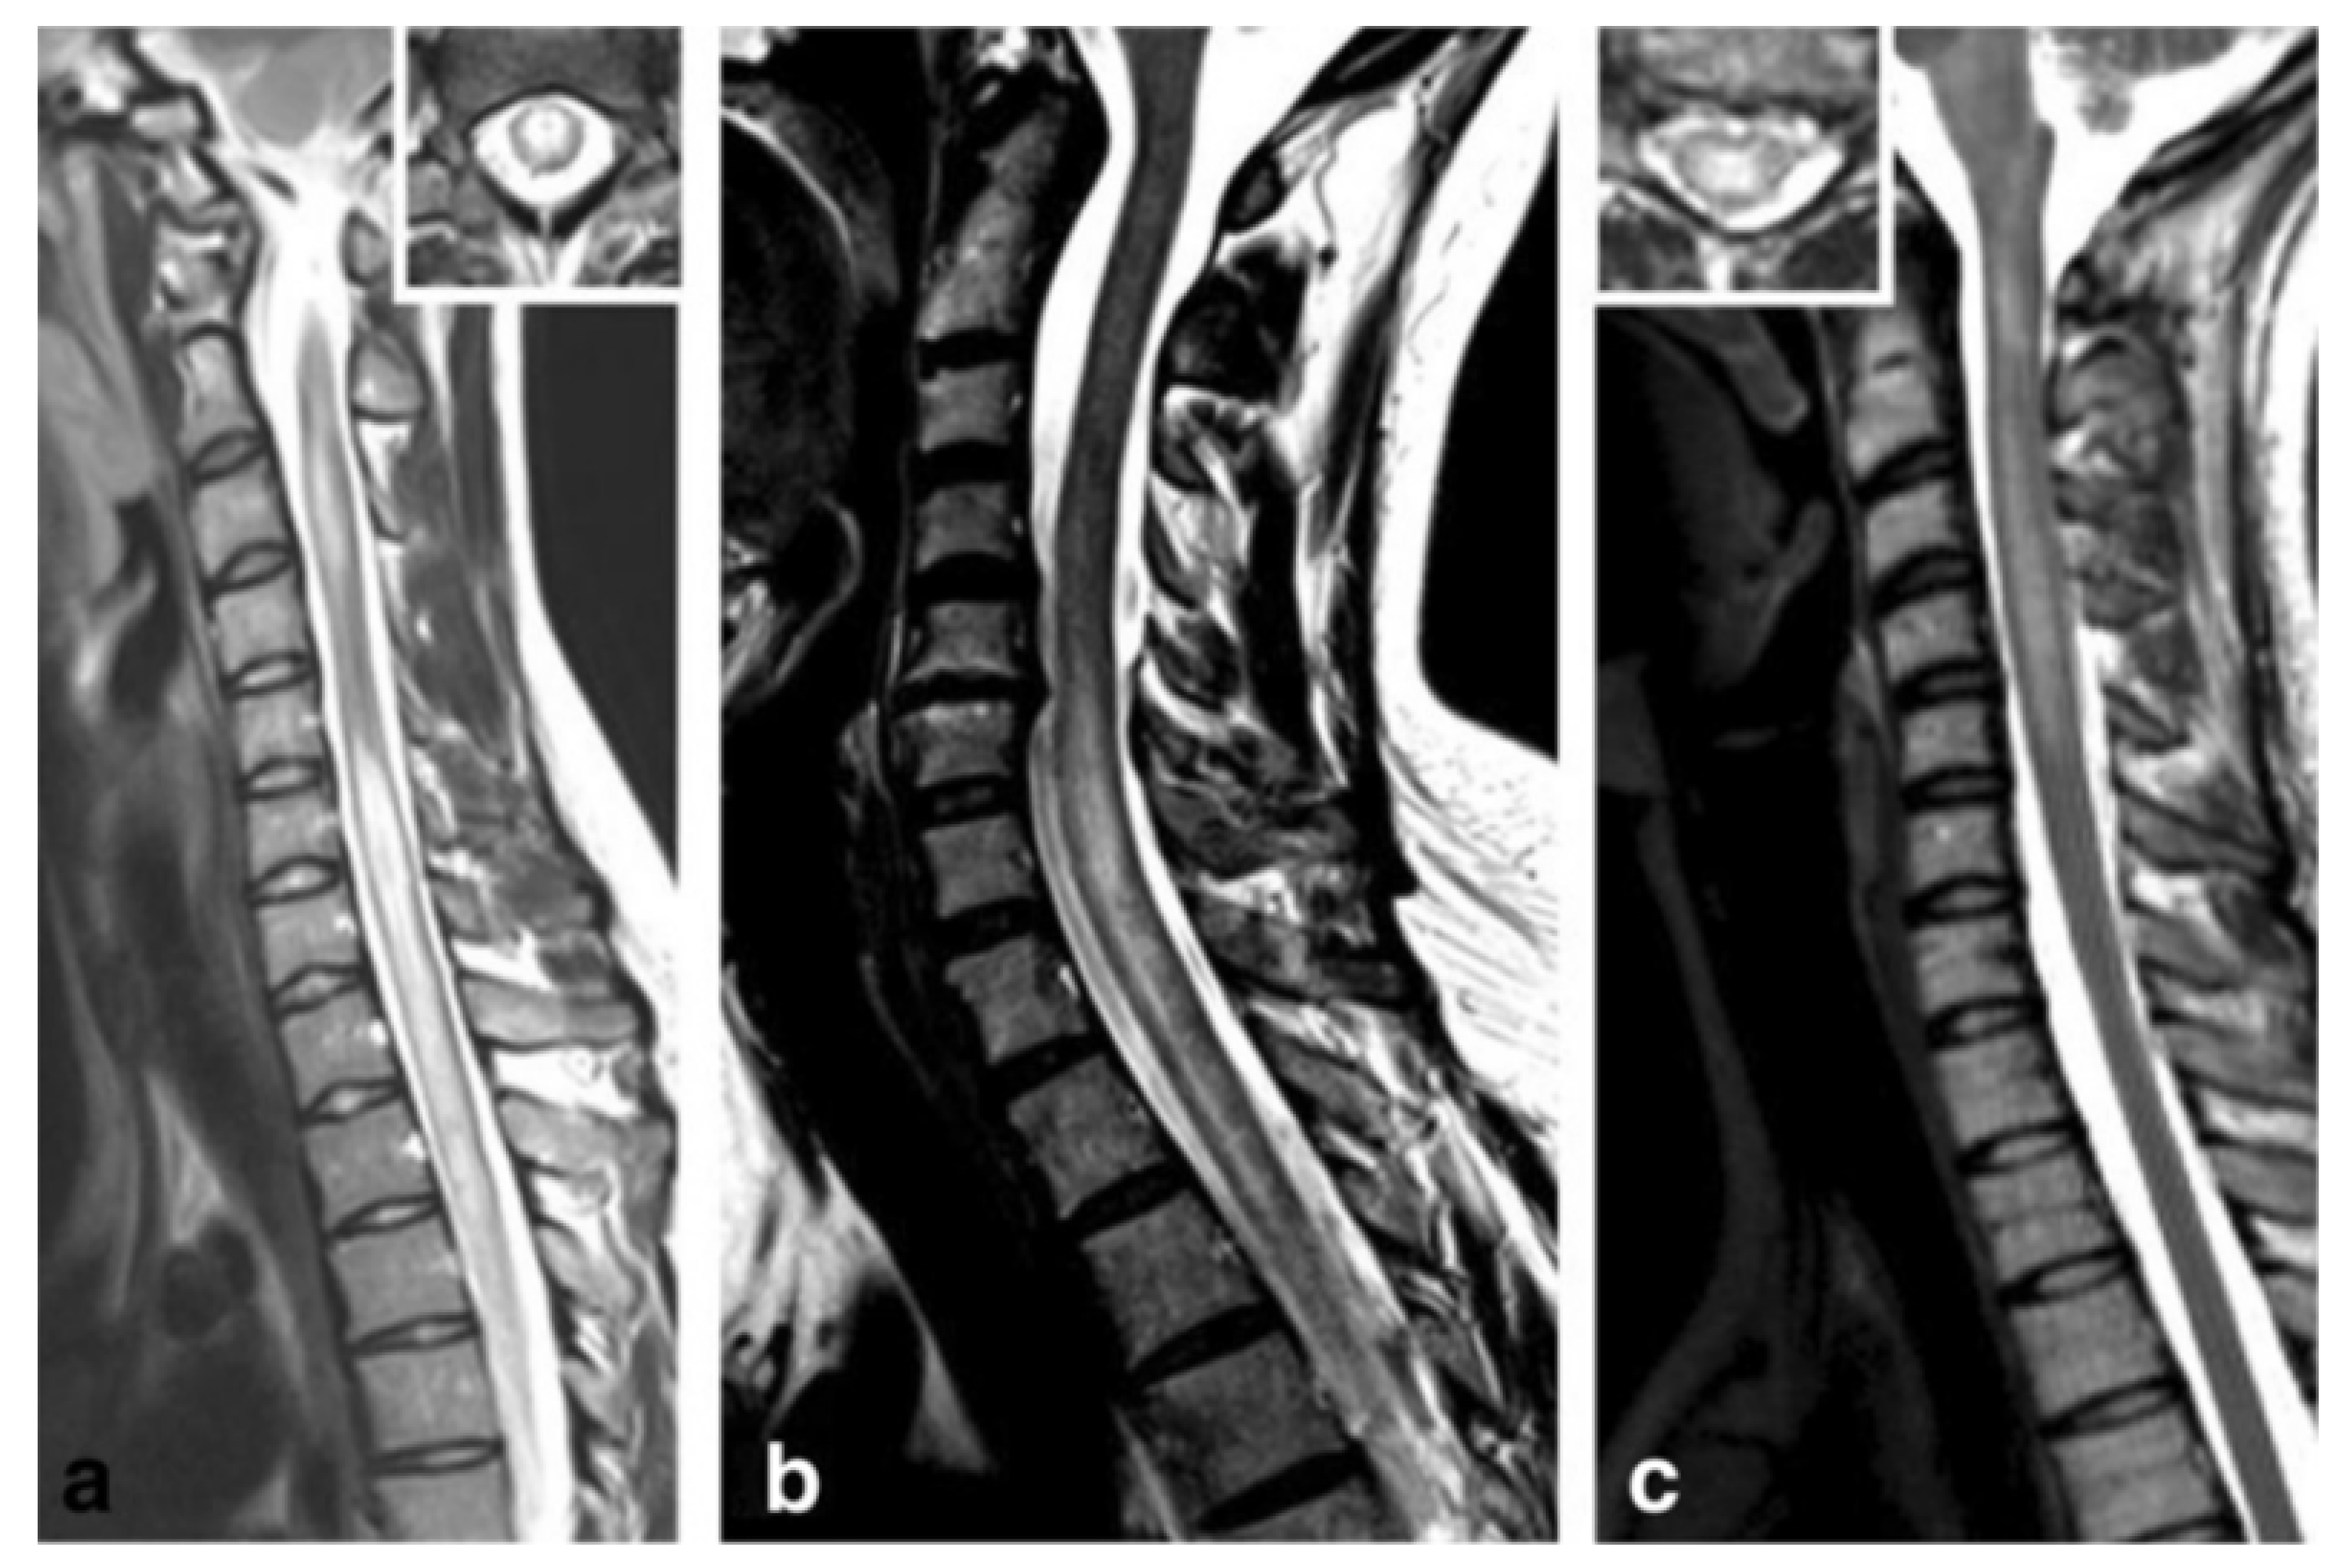

Figure 3.

Anti-myelin oligodendrocyte glycoprotein (MOG) antibody myelitis. (a) Sagittal T2-weighted spinal MRI performed at disease onset revealed a large longitudinal centrally-located lesion extending over the entire spinal cord, as well as swelling of the cord. (b) Longitudinally extensive central spinal cord T2 lesion in another patient. (c) T2-hyperintense lesions extending from the pontomedullary junction throughout the cervical cord to C5, in a third patient. Insets in (a) and C show axial sections of the thoracic cord at lesion level [172]. Figure is extracted from Jarius, S. et al., J Neuroinflammation 2016, 13, 280 (http://creativecommons.org/licenses/by/4.0/).

Approximately half the patients with MOG ab-associated disease present episodes involving the spinal cord [177,178]. The most common symptoms include paraparesis, and sensory and sphincter dysfunction. On MRI, LETM is frequent and short myelitis less common. Any segment of the spinal cord can be affected, although lesions are more frequent in the thoracolumbar and/or conus medullaris regions, as opposed to the more common cervicothoracic involvement observed in AQP4 ab positive and MS myelitis cases [178,179]. Anti-MOG ab associated myelitis is hyperintense on T2-weighted and iso-hypointense on T1-weighted sequences, showing contrast enhancement during acute phases in up to 70% of cases [172]; Figure 3 and Figure 4. MOG ab-related disease does not commonly result in cord necrosis or cavitations as observed in AQP4-mediated cases [134,175,178]. Due to the predilection for conus localization, bladder, bowel, and erectile dysfunction is observed in approximately 70% of patients [167]. In comparison to AQP4-IgG+ NMOSD, MOG ab disease myelitis appears to more focal and with better clinical outcome, although poor outcome with permanent disability has been described for both conditions [156]. Notably, anti-MOG ab serum titers follow disease activity levels, with significantly higher concentration during acute attacks than remission, further supporting the concept of their pathogenic role [172].